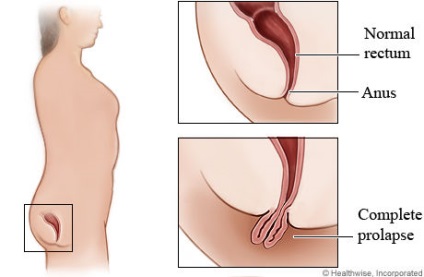

A Google fordítója a "prolapsus" szó 2 jelentését adja ki - kihagyva, kihagyva.

A képkeresés a kardiológus váratlan eredményéhez vezet. Kiderül, hogy a prolapsus más szervekben, különösen a végbélben fordul elő.

Itt vannak a leginkább ártatlan képek a "rektális prolapsus" kérésére. Ez a rendszer:

És ez az élet:

Ebből arra következtethetünk, hogy az elörelépés a szerv nyilvánvalóan patológiás elmozdulása a normál anatómiai helyén.